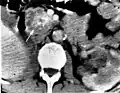

Pancreatic serous cystadenoma

Pancreatic serous cystadenoma is a benign tumour of the pancreas.[2] It is usually solitary and found in the body or tail of the pancreas, and may be associated with von Hippel–Lindau syndrome.[2]